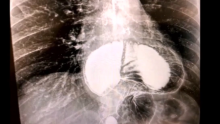

The accompanying video details a retrospective review performed on patients who had robotic AFR (RAFR) of large HH. All patients received the previously validated gastroesophageal reflux disease-health-related quality of life (GERD-HRQL) questionnaire preoperatively and postoperatively. Objectively, symptoms were graded using the Visick scale Recurrence was defined as greater than 2 cm or 10% of the stomach above the diaphragm detected by either CT, esophagogram, or endoscopy. The preoperative data was then compared to the results at two years.

The results showed that of the 396 patients who underwent RAPR, the median GERD-HRQL score was 42 (range 38–45) preoperatively and 6 (range 0–14) at two years (p < 0.05). Preoperatively, 87 percent of patients were graded as Visick IV. At two years, 95 percent were graded as Visick I. HH recurrence occurred in four out of the 396 patients, or just 1 percent.